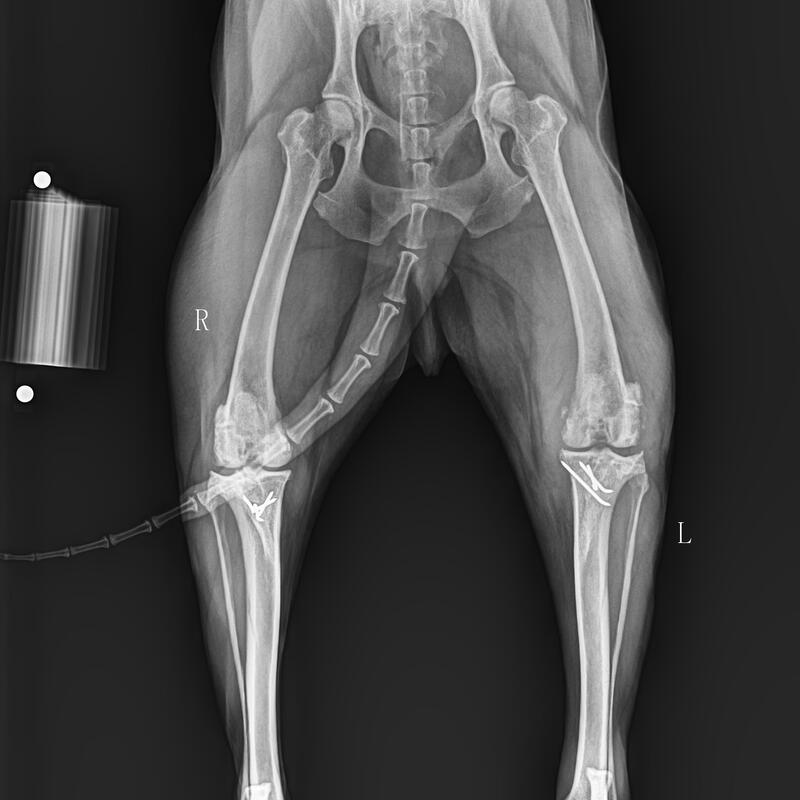

Species: Husky dog

Nickname: NIMO

Age: 9 years old

Gender: Male

Weight: 26.5 Kg

Severe arthritis, left hind limb swollen and limping. Three years ago, bilateral meniscal groove deepening + tibial tuberosity repositioning surgery was performed. After the surgery, the left hind limb did not recover well, and bilateral knee joints had severe arthritis. A decision was made to undergo PGRsurgery for treatment. During the operation, the BlueSAO biological PGRSystem#9 implant was used for replacement. The surgery was successfully completed. Hope a speedy recovery.

Thanks to Dr.Guan Narisufrom Shanghai Shengtai Pet Hospital, for sharing the clinical case of the BlueSAO biological press-fit PGR system!